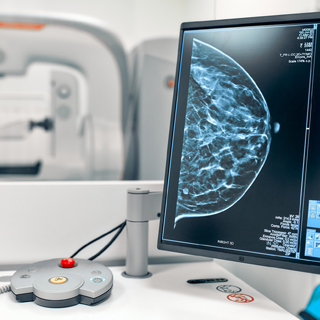

Modern Equipment

We use the first-class medical equipment for timely diagnostics of various diseases.

All Kinds

of Diagnostics

Offering most comprehensive range of pathology & radiology testing services from routine lab tests to technologically advanced tests